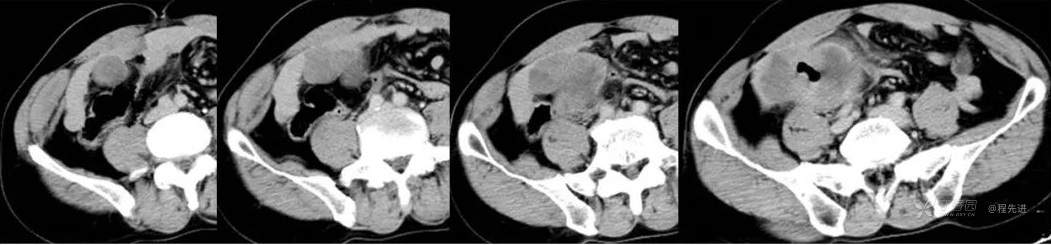

门静脉期